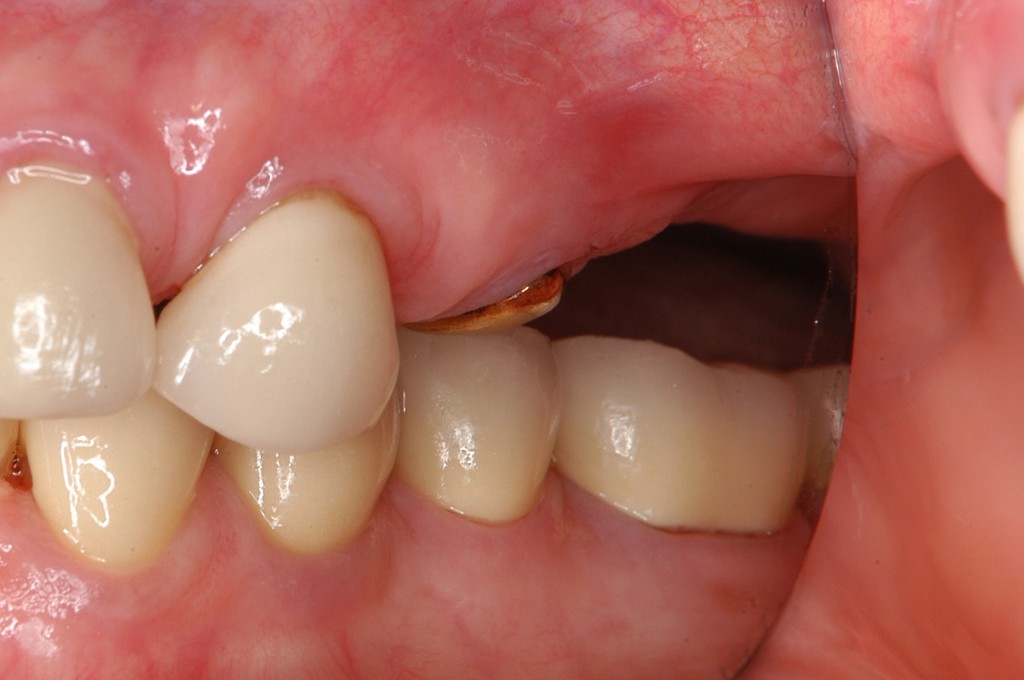

上の奥歯にインプラント治療をしたいが骨が全く無く,前の歯科医師にはインプラントは無理と言われたとのこと。

まずはインプラントを支えるための骨を造る必要がありましたので,サイナスリフトという手術を行いました。

インプラントを埋入し,セラミックスクラウンを被せました。